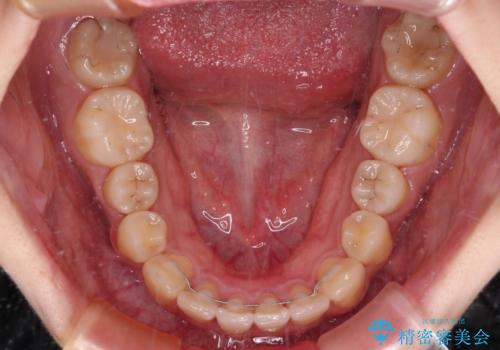

しっかりと装着時間を守ってくださったので、予定通り1年強で治療を終えることができました。